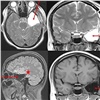

До операции пациент проходит ряд специфических обследований: длительный видео-электроэнцефалографический мониторинг, воздействия, провоцирующие эпилептический приступ: гипервентиляцию, фотостимуляцию на фоне отмены антиконвульсантов, депривацию сна (недостаток или полное отсутствие сна), исследование электроэнцефалограммы больного в состоянии физиологического сна. Комплексное обследование помогает врачам установить локализацию участка мозга, который провоцирует приступы. Также с пациентами работает нейропсихолог для оценки рисков ухудшения памяти и когнитивного статуса в случае проведения операции.